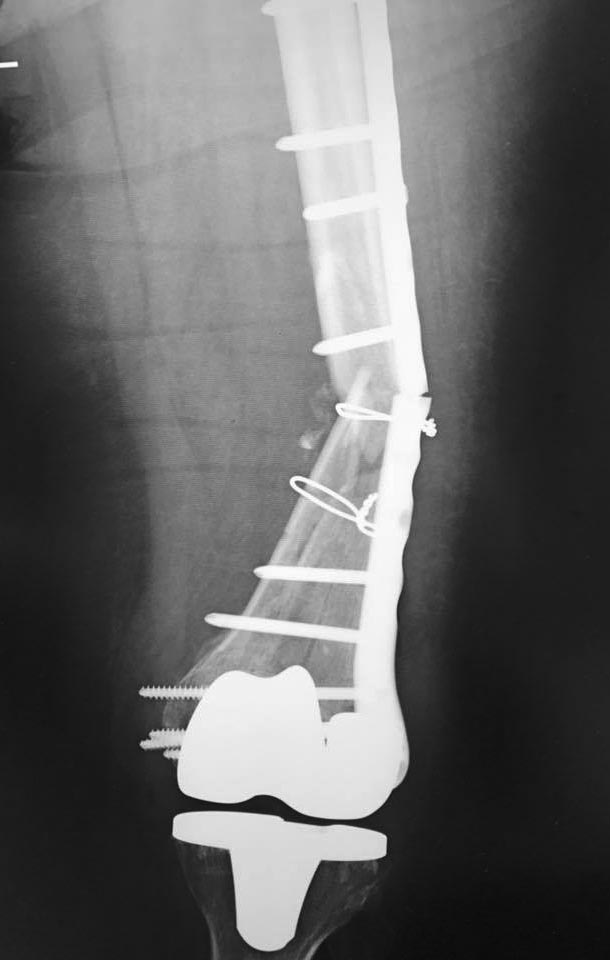

Re: Перипротезный перелом дистального отдела бедра

Итак, она вчера опять сломала ногу и пластину тоже! Комментарии продолжаются...